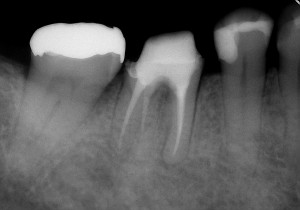

初診時は、時々歯肉から膿が出てきたり、鈍痛を感じることがあったとのこと。レントゲン写真を見ると確かに病気が出来ている影が・・・。さらに、この影の形を見るともしかしたら歯の根が割れているかもしれない。そうなると抜歯に移行しなければなくなる可能性もあることなど病気が治る喜びだけでなく、リスクや起こりうる可能性についても細かく説明させていただいた後に治療を開始しました。

↑初診時